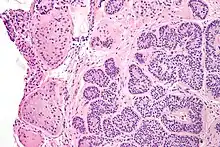

Micrograph of a Sertoli cell nodule. H&E stain. | |

Sertoli cell nodules are unencapsulated nodules that consist of:[2][3][4]

- cells arranged in well-formed tubules (that vaguely resemble immature Sertoli cells), with

- bland hyperchromatic oval/round nuclei that are stratified, and

- may contain eosinophilic (hyaline) blob in lumen (centre).